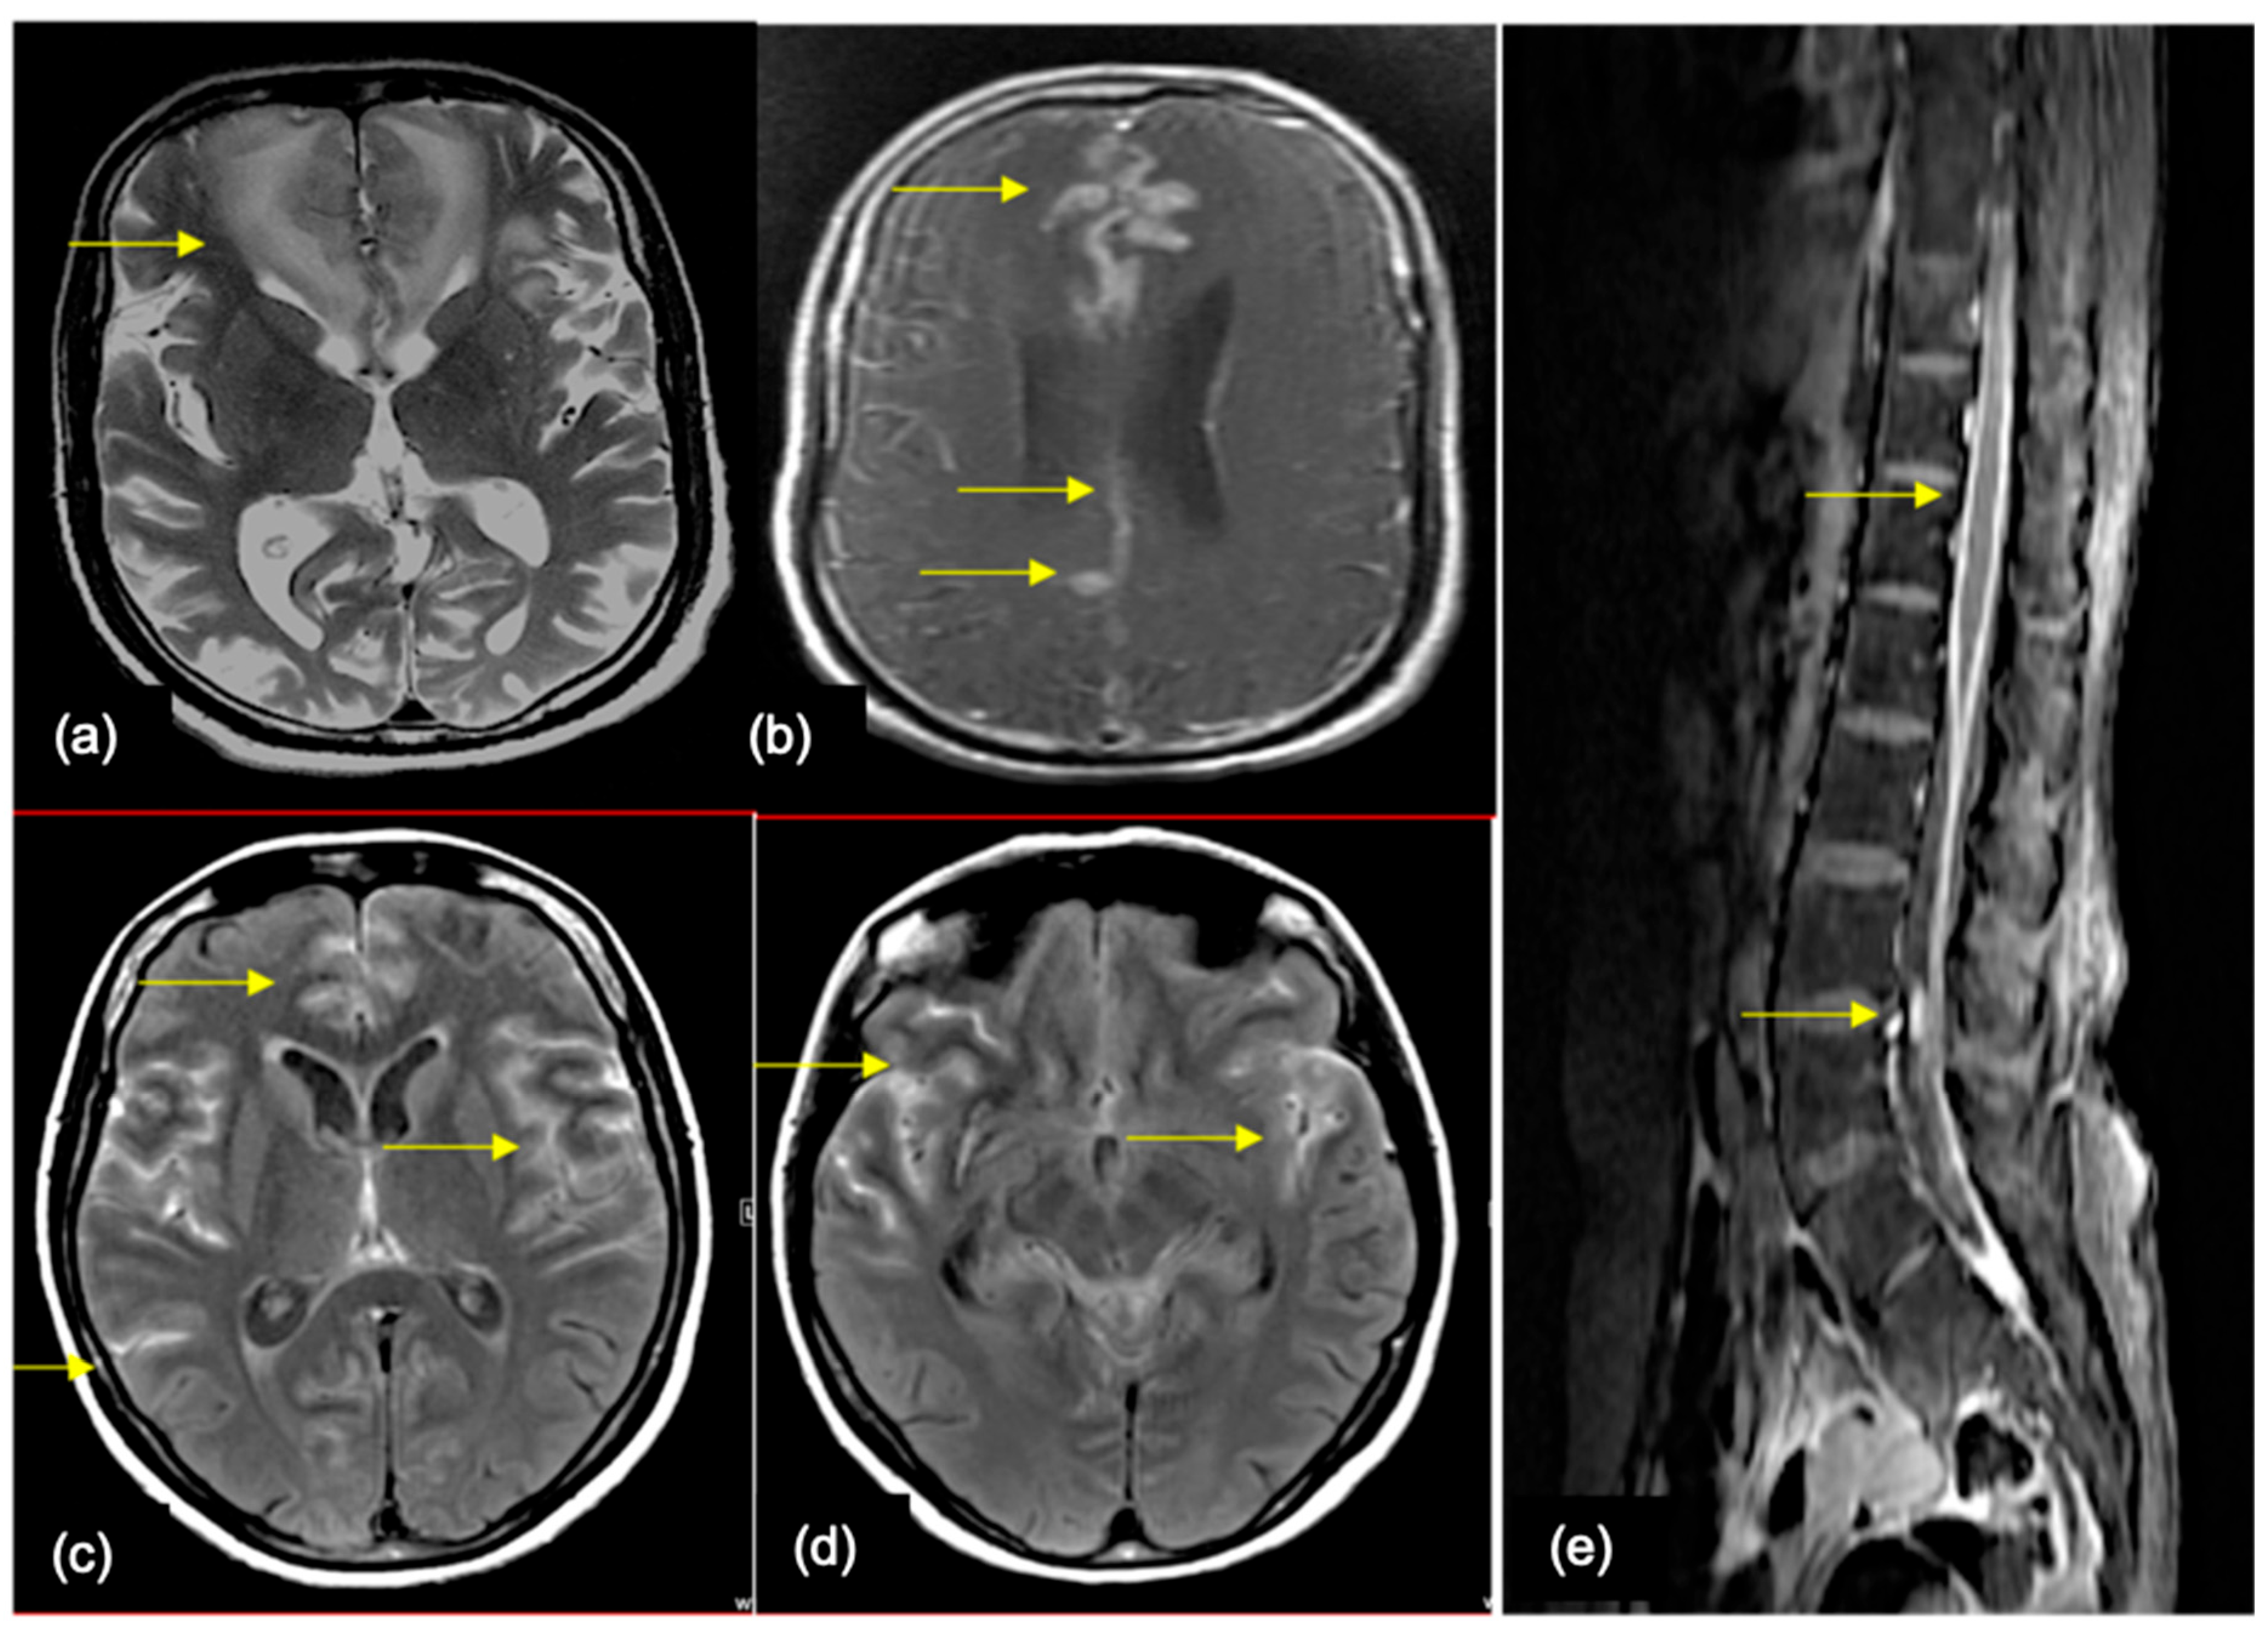

8. Spine Imaging

11. Imaging Findings

12. Work-Up